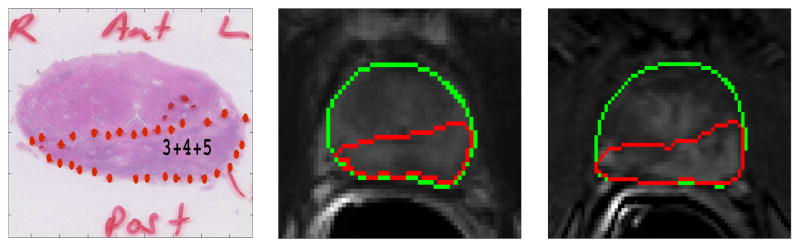

Our tissue cutting protocol and device ensured that the histopathology slides and the T2-weigthed MR slices could be matched. However, due to shrinkage of the tissue after surgery, deformable registration was required to map the histology findings to the MR images. Registration of DCE images to T2-weighted images were also needed to compensate for the motion of the prostate during the prolonged DCE MRI scan. The whole-mount pathology slides were registered with the corresponding T2-weighted MR images by affine registration followed by deformable B-spline registration. T2-weighted images were also registered to the corresponding DCE-MR images following similar procedures. These two transformations were used successively on the pathology slides to register it to DCE-MR images. To register the images, the prostate region was manually segmented in both the fixed (MRI) and the moving images and registration was applied on the segmented region only. Mutual information was used as the similarity measure and adaptive stochastic gradient descent was used as the optimizer to guide the registration process. After registration, the computed transformations were applied to map tumor regions from the pathology slides to the corresponding T2-weighted and DCE-MR images. For registration, we used elastix, which is an open source software for image registration [31]. We used Dice Similarity Coefficient (DSC) to validate the registration. The average DSC value between the pathology and T2-weighted images after registration was 0.94, and between registered T2-weighted and DCE image it was 0.95. Fig. 2 and 3 show two cases where the tumor regions from the pathology slides are mapped to the corresponding T2-weighted and DCE MRI slices.

Figure 2.

Registration example 1: Peripheral zone tumor from pathology slide (left) was mapped to the corresponding T2-weighted (middle) and DCE-MRI slice (right). The green contour represents the boundary of the prostate gland.

Figure 3.

Registration example 2: Peripheral zone tumor from pathology slide (left) was mapped to the corresponding T2-weighted (middle) and DCE-MRI slice (right). The green contour represents the boundary of the prostate gland.